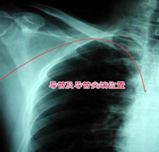

拍胸片定位,如有異常護士會(huì)根據具體情況進(jìn)行處理